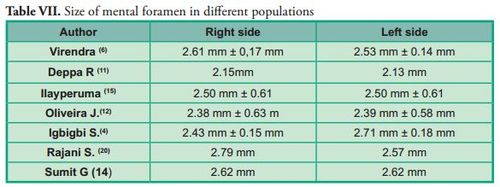

The size of the mental foramen was classified into 5 ranges. In most cases, they were located in the 2 mm to 2.99 mm range on both sides, with a frequency of 75 cases (41.7%) on the right side and 78 cases (43.3%) on the left side.

Several authors have evaluated the size of the mental foramen on dry mandibles. Their results are similar to the results of this study: within the 2 mm to 2.99 mm range (Table VII).

The size of the mental foramen was classified into 5 ranges. In most cases, they were located in the 2 mm to 2.99 mm range on both sides, with a frequency of 75 cases (41.7%) on the right side and 78 cases (43.3%) on the left side.

Several authors have evaluated the size of the mental foramen on dry mandibles. Their results are similar to the results of this study: within the 2 mm to 2.99 mm range (Table VII).